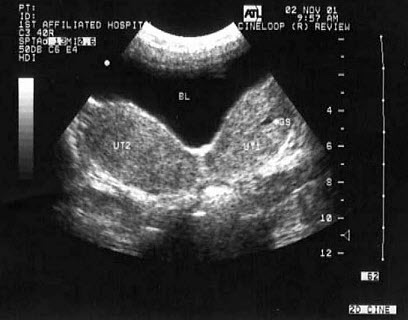

20、单项选择题

女,26岁,停经3个月,HCG阳性。根据B超检查声像图如下,最可能的诊断为()